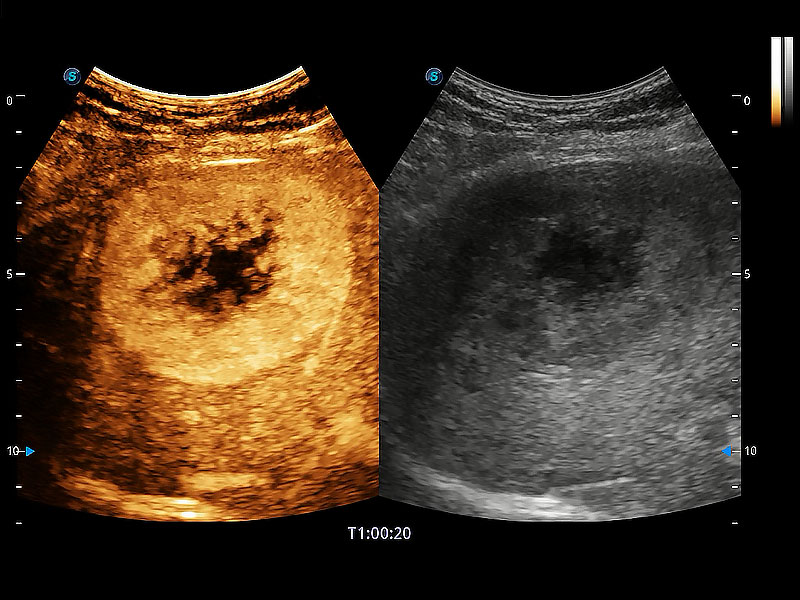

非線性融合造影成像充分利用諧波和基波信號,為難以觀察的血流進(jìn)行增強(qiáng)顯像??捎糜诰€陣、凸陣、微凸陣、相控陣探頭。